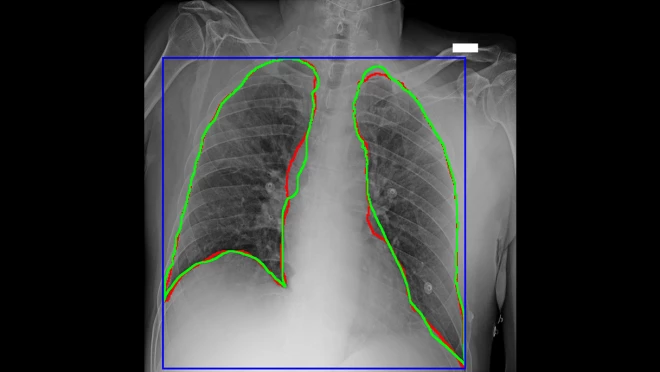

由Centro Diagnostico Italiano和Bracco Imaging领导的医疗和研究组织联盟,协同创建了AIforCOVID影像档案,这是一个拥有近1000张胸部X光片和新冠肺炎患者匿名临床数据的存储库。联盟内的多家研究机构开发了三种机器学习方法,可以在亚马逊云科技上对这些图像和临床数据进行分析。基于这些分析,联盟开发了一个模型,能够通过胸部X光图像和临床数据,预测新冠肺炎患者的临床结果。AIforCOVID网络收集的所有数据都放在项目网站(https://aiforcovid.radiomica.it/),供国际科技界的成员下载。

图4  AlforCOVID项目的新冠患者胸部X光片,对感染区域的AI划线(红色)与手工划线(绿色)很接近

“在对新冠患者的管理中,放射影像学对诊断和治疗方案起着至关重要的作用。得益于亚马逊云科技的技术和专业支持所带来的机器学习力量,我们已经能够快速理解诊断成像和临床分析所产生的大量数据。我们正在努力提供实用的资源,世界各地的医院和组织可以应用这种资源,增加对疾病的理解,促进自己的诊断工作,改善患者治疗。”意大利诊断中心影像诊断和立体定向放射外科主任Sergio Papa表示。